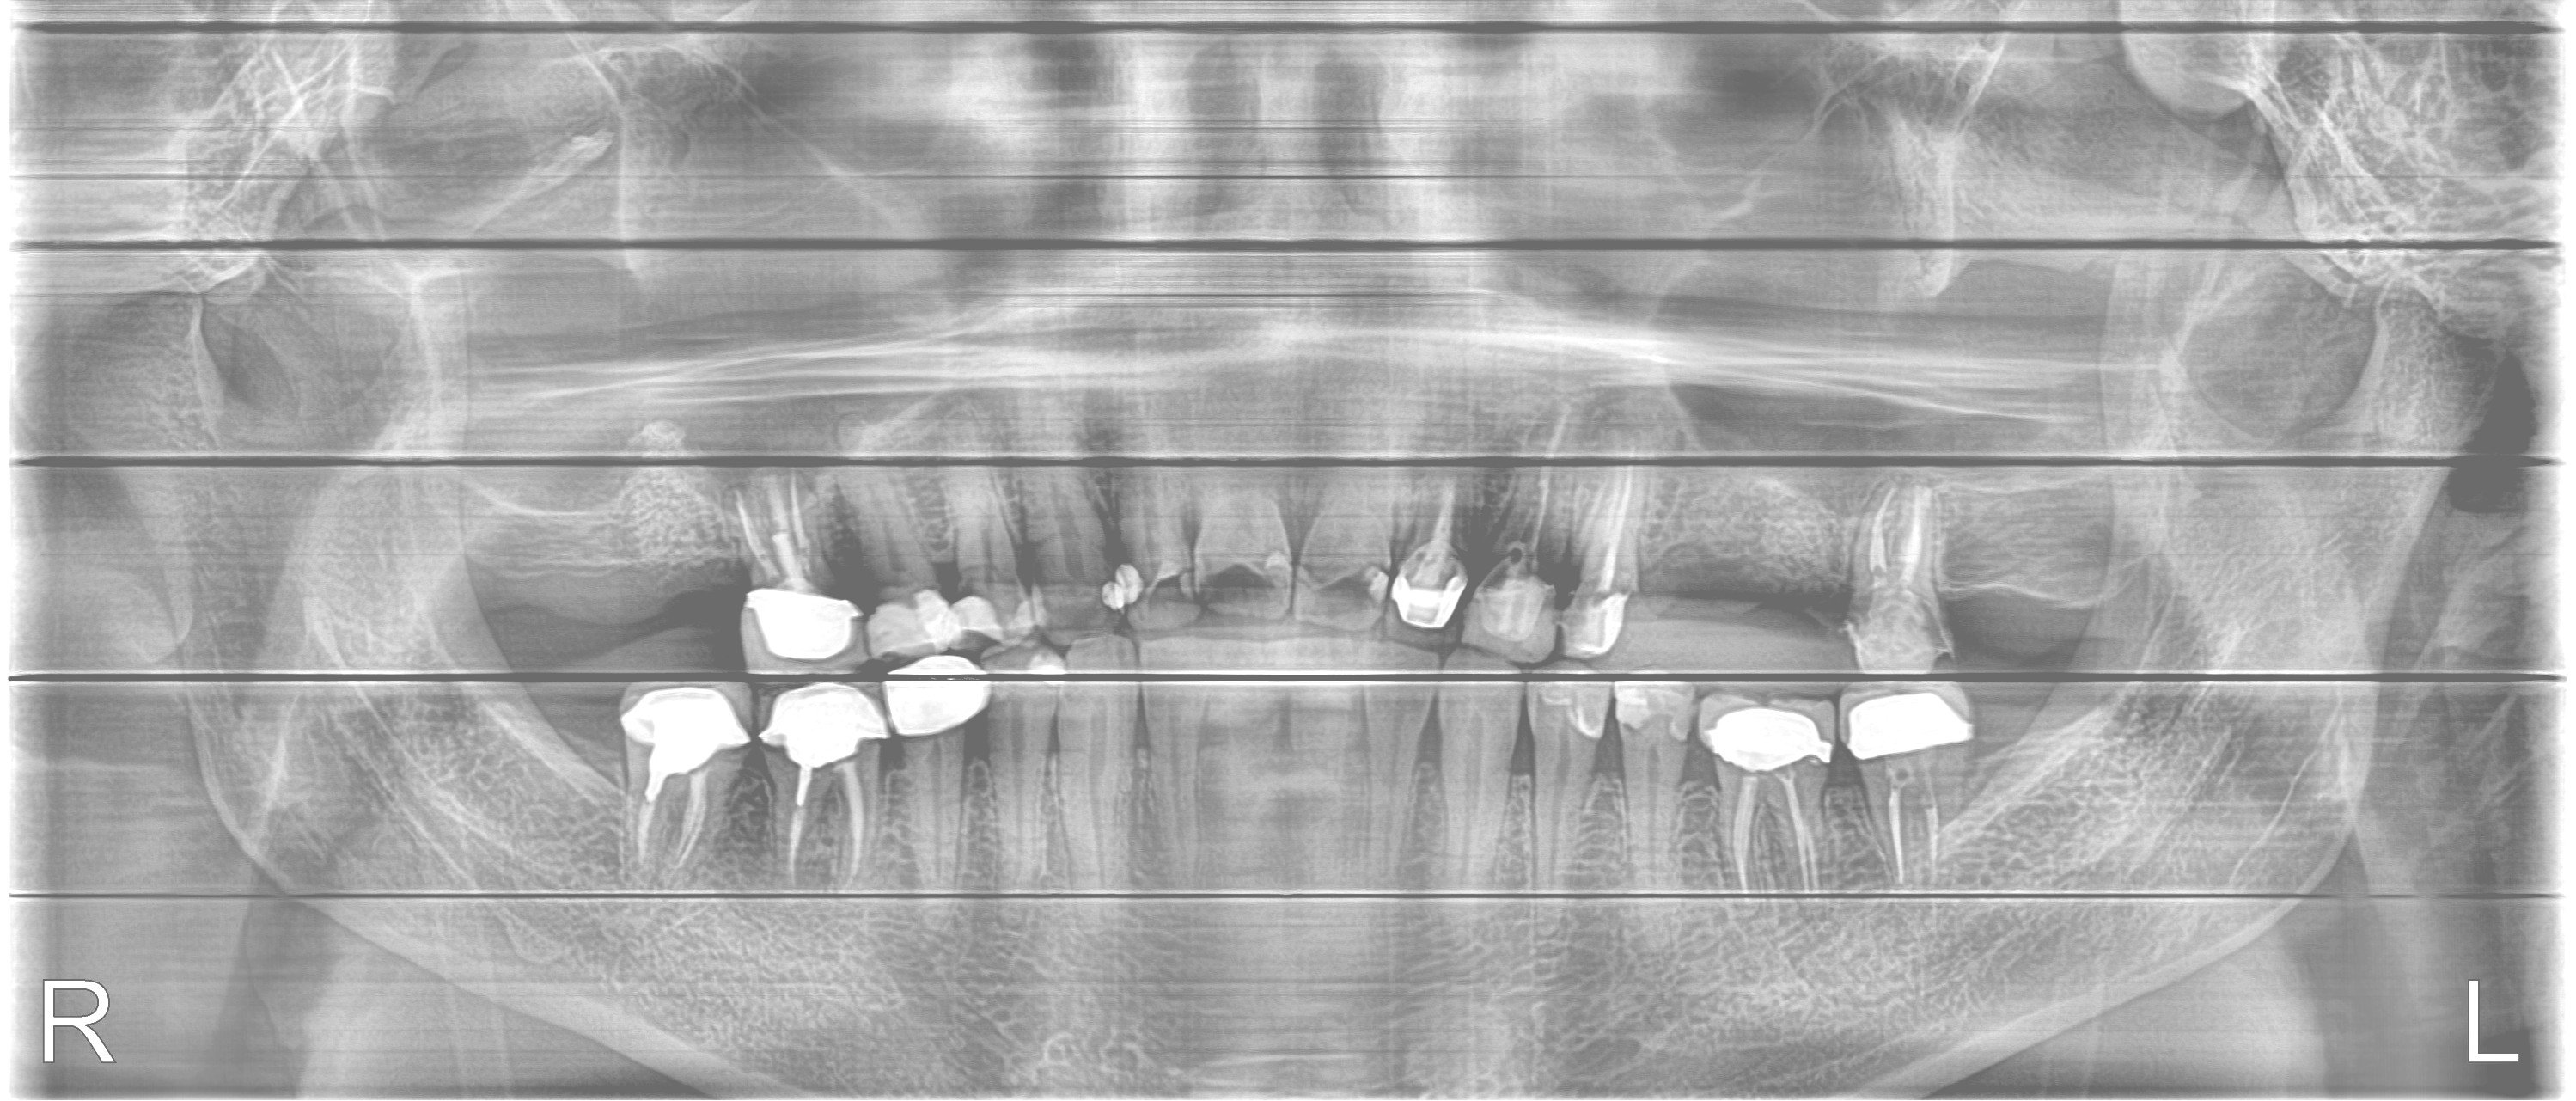

患者於原診所處理牙齒,僅是補牙、抽神經、做假牙的無限輪迴,牙齒壞了做牙橋,牙橋壞了補骨準備植牙,但因患者有疑慮,牙齒始終做不好,上顎假牙總是脫落、總是在看牙醫;決心換家評估。在聽過醫師仔細的分析後,決心要改變自己之前的觀念,接受醫師全口重建的治療方式。

這才發現原來補骨醫師技術有別,不是有補就好,蛀牙也不是一再重複處理讓牙齒神經反覆受刺激;需要先處理咬合、排列的問題,再將缺牙、蛀牙和前牙美觀合併處理,不但解決了牙縫塞東西造成蛀牙不斷,也讓牙齒排列改變改變外觀。

改變排列及牙齒上下相對位置,才能讓咬合和受力分配較佳並穩定,不會產生牙縫遭受直接衝擊的問題。

補骨後再植牙,讓牙齒地基有足夠的骨本,也讓自己擺脫總是在做假牙或做假牙的路上的命運。